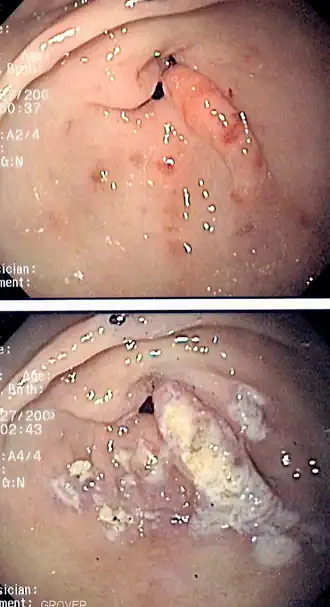

![]() Imagen de endoscopia de la ectasia vascular antral gástrica vista como un patrón radial alrededor del píloro antes (arriba) y después (abajo) del tratamiento con coagulación con plasma de argón. | ||

La GAVE se trata comúnmente por medio de un endoscopio, incluida la coagulación con plasma de argón y electrocauterio.[11][10][22] Dado que la endoscopia con fotocoagulación con argón es "generalmente efectiva", la cirugía "generalmente no es necesaria".[10] La terapia de coagulación es bien tolerada pero "tiende a inducir supuración y sangrado".[10] La "endoscopia con ablación térmica" es el tratamiento médico preferido debido a sus bajos efectos secundarios y baja mortalidad, pero "rara vez es curativa".[11] El tratamiento de la GAVE puede clasificarse en endoscópico, quirúrgico y farmacológico. El tratamiento quirúrgico es definitivo, pero rara vez se realiza hoy en día con la variedad de opciones de tratamiento disponibles. Algunas de las modalidades comentadas se han utilizado en pacientes con GAVE con otra enfermedad subyacente. El tratamiento sintomático incluye la administración de suplementos de hierro y la transfusión de sangre para los casos con anemia grave, los inhibidores de la bomba de protones pueden mejorar la gastritis crónica de fondo y las erosiones diminutas que suelen coexistir en los informes de las biopsias.